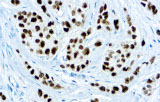

Gli anticorpi primari contro il recettore degli estrogeni (ER), recettore del progesterone (PR), HER2 e Ki-67 rimangono il pilastro della classificazione e delle decisioni terapeutiche nel cancro al seno. Questi anticorpi sono validati clinicamente e marcati CE/IVD per garantire una rilevazione affidabile e riproducibile dei biomarcatori – cruciale per guidare la terapia ormonale e le strategie di trattamento mirato.